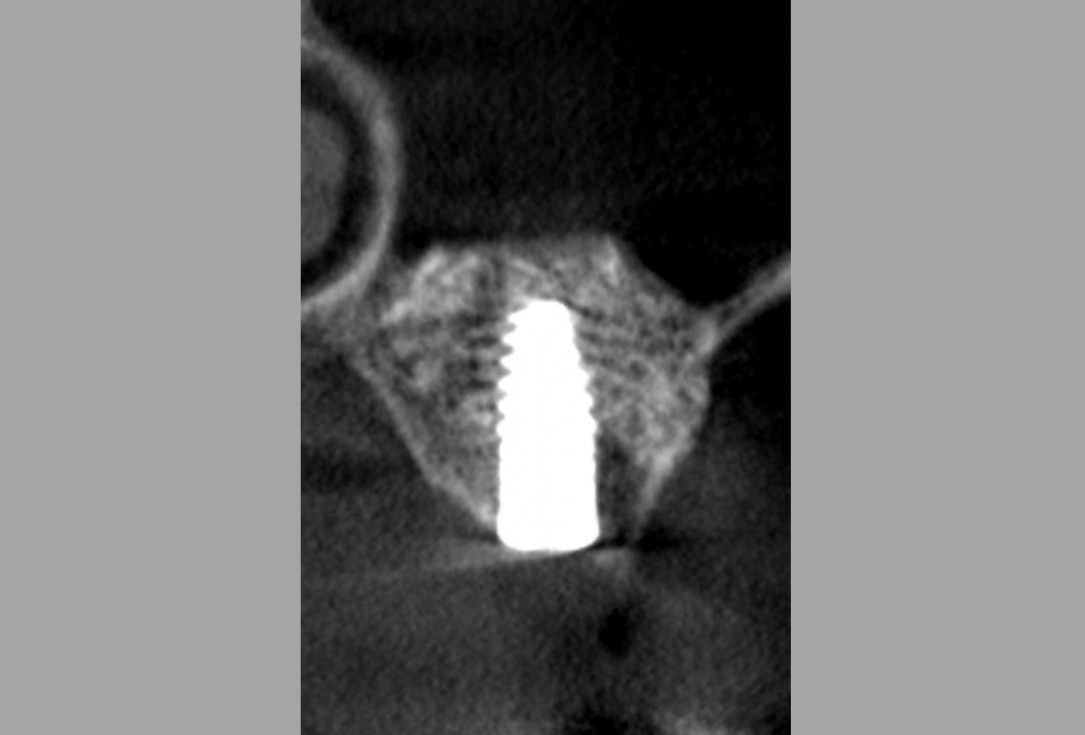

16/16 - Alveolar ridge and sinus floor CT scan after 6 months healing time

Lateral sinus lift one-stage with cerabone® & collprotect® membrane - Dr. V. Kalenchuk